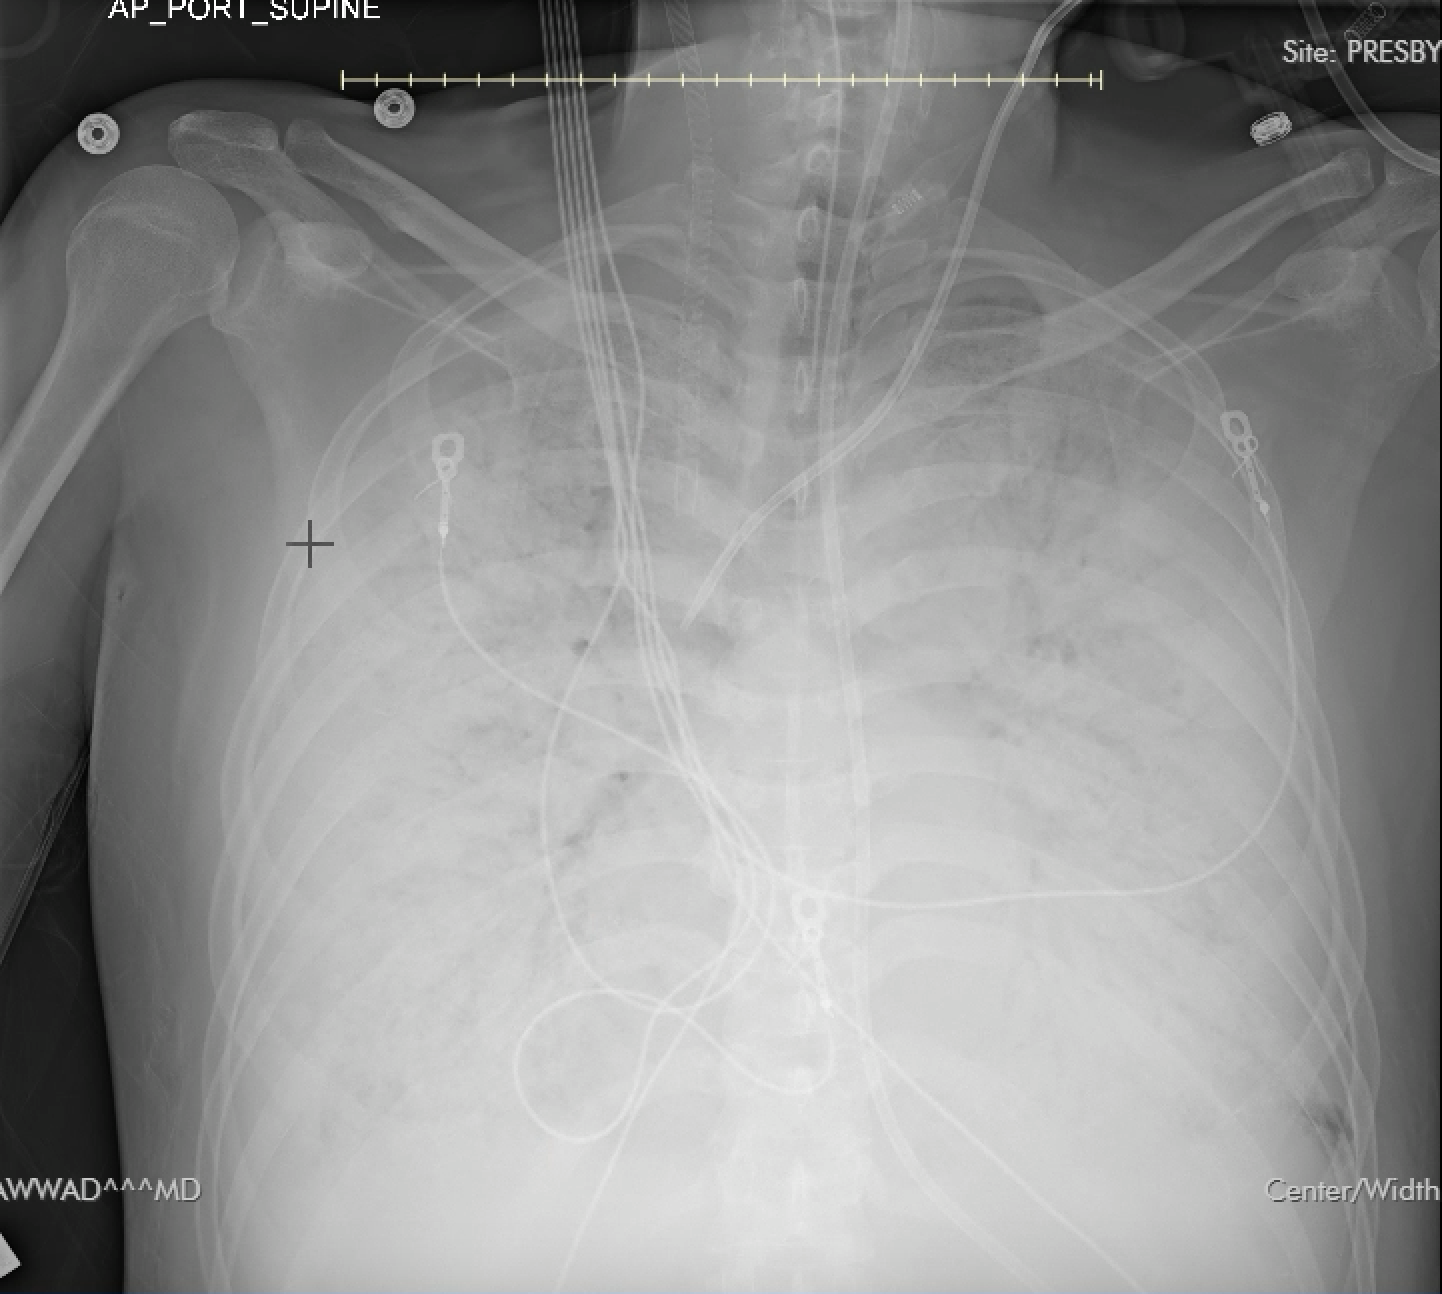

Case Presentation: A 53-year-old Vietnamese monk living in a rural Texas monastery presented with fatigue, muscle aches, and fever that progressed to respiratory distress after a two-week delay in seeking care. He was intubated and sedated at a tertiary care center. He was afebrile, tachycardic (HR 122 bpm), and normotensive. Labs showed a leukocytosis (WBC 22.5k), creatinine 1.29, troponin 0.127, and platelets 217k Imaging revealed diffuse bilateral pulmonary opacities and lower lobe edema. Chest X-ray revealed infiltrates suspicious for pulmonary edema. The differential diagnosis included community-acquired pneumonia and an unlikely differential of Hantavirus Pulmonary Syndrome (HPS), given that he lived in a rural monastery with outside grain storage. It was later determined that another monk in the monastery had died from similar symptoms. The patient was treated with broad-spectrum antibiotics and started on assist-control ventilation (FiO2 100%, PEEP 14). Worsening hypoxia resulted in the use of pressure control ventilation with high PEEP, proning, and paralysis. He continued to decline and remained hypoxic on maximal ventilator settings. On day 7, venous-venous (VV) ECMO was initiated due to hypoxemic respiratory failure. Echocardiography revealed severe mitral regurgitation with posterior leaflet prolapse, requiring LV offloading with an LVAD. Due to concern for lack of improvement on steroids and antibiotics, hantavirus serology was sent. He developed a worsening leukocytosis (20.56k), thrombocytopenia (33k), coagulopathy (aPTT of 110.7), and shock liver (AST 1,112, ALT 478). Labs also showed severe metabolic acidosis (pH 6.97). Repeat Chest X-ray showed ARDS. Hantavirus IgM confirmed HPS on day 14. Despite transient improvement, the patient required multiple vasopressors and progressed to multi-organ failure. The family opted for comfort measures, and care was withdrawn.